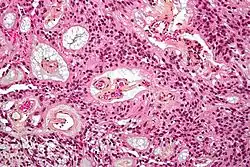

| Micrograph of an ependymoma. H&E stain. | |

Ependymomas are composed of cells with regular, round to oval nuclei. There is a variably dense fibrillary background. Tumor cells may form gland-like round or elongated structures that resemble the embryologic ependymal canal, with long, delicate processes extending into the lumen; more frequently present are perivascular pseudorosettes in which tumor cells are arranged around vessels with an intervening zone consisting of thin ependymal processes directed toward the wall of the vessel.[5]

It has been suggested that ependymomas are derived from radial glia, despite their name suggesting an ependymal origin.[6]